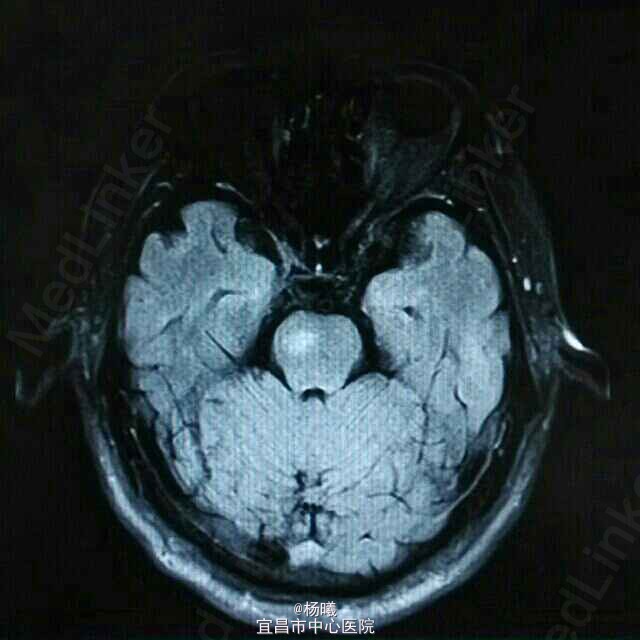

查体:BP 136/84mmHg,抬腿右下肢较左侧差,余无明显异常。 辅检:6-8 D-D 1.87,FIB 7.15,ALT 38,AST 46,GGT 37,LDL-C 4.38,铁蛋白 320,CRP 96.7,ESR 70,尿酮体1+ 6-15 PLT 469,ALT 53,GGT 50,ESR 38,D-D 0.59 血糖监测:早餐后高 彩超多普勒:升主动脉较宽,左室舒张功能减低;双侧颈动脉粥样硬化斑形成。 经颅多普勒:双侧颈内动脉、颈外动脉、左侧颈总动脉血流速度减慢;左侧锁骨下动脉、右侧大脑中动脉、大脑前动脉、左侧颈内动脉虹吸部管腔呈收缩状态;左侧颈内动脉虹吸部管腔重度狭窄;各检查动脉管腔应硬化。 头部MR、脑动脉造影MRA:脑干右侧11*12mm梗塞灶;腔隙性脑梗塞;脑萎缩;双侧额部顶部硬膜下积液;左侧椎动脉起始段及椎动脉-基底动脉汇合段管腔中度狭窄,双侧颈总、颈内外动脉、双侧大脑前中后动脉多发中-重度狭窄,动脉粥样硬化表现。

诊断:脑梗塞;高血压病3级 极高危;糖尿病 2型;动脉粥样硬化;高脂血症;慢性胃炎 治疗:依达拉奉、马来酸桂哌齐特、丹森川穹嗪注射,小牛血清去蛋白注射液;硝苯地平缓释片;阿司匹林肠溶片;阿托伐他丁钙片;阿卡波糖片。